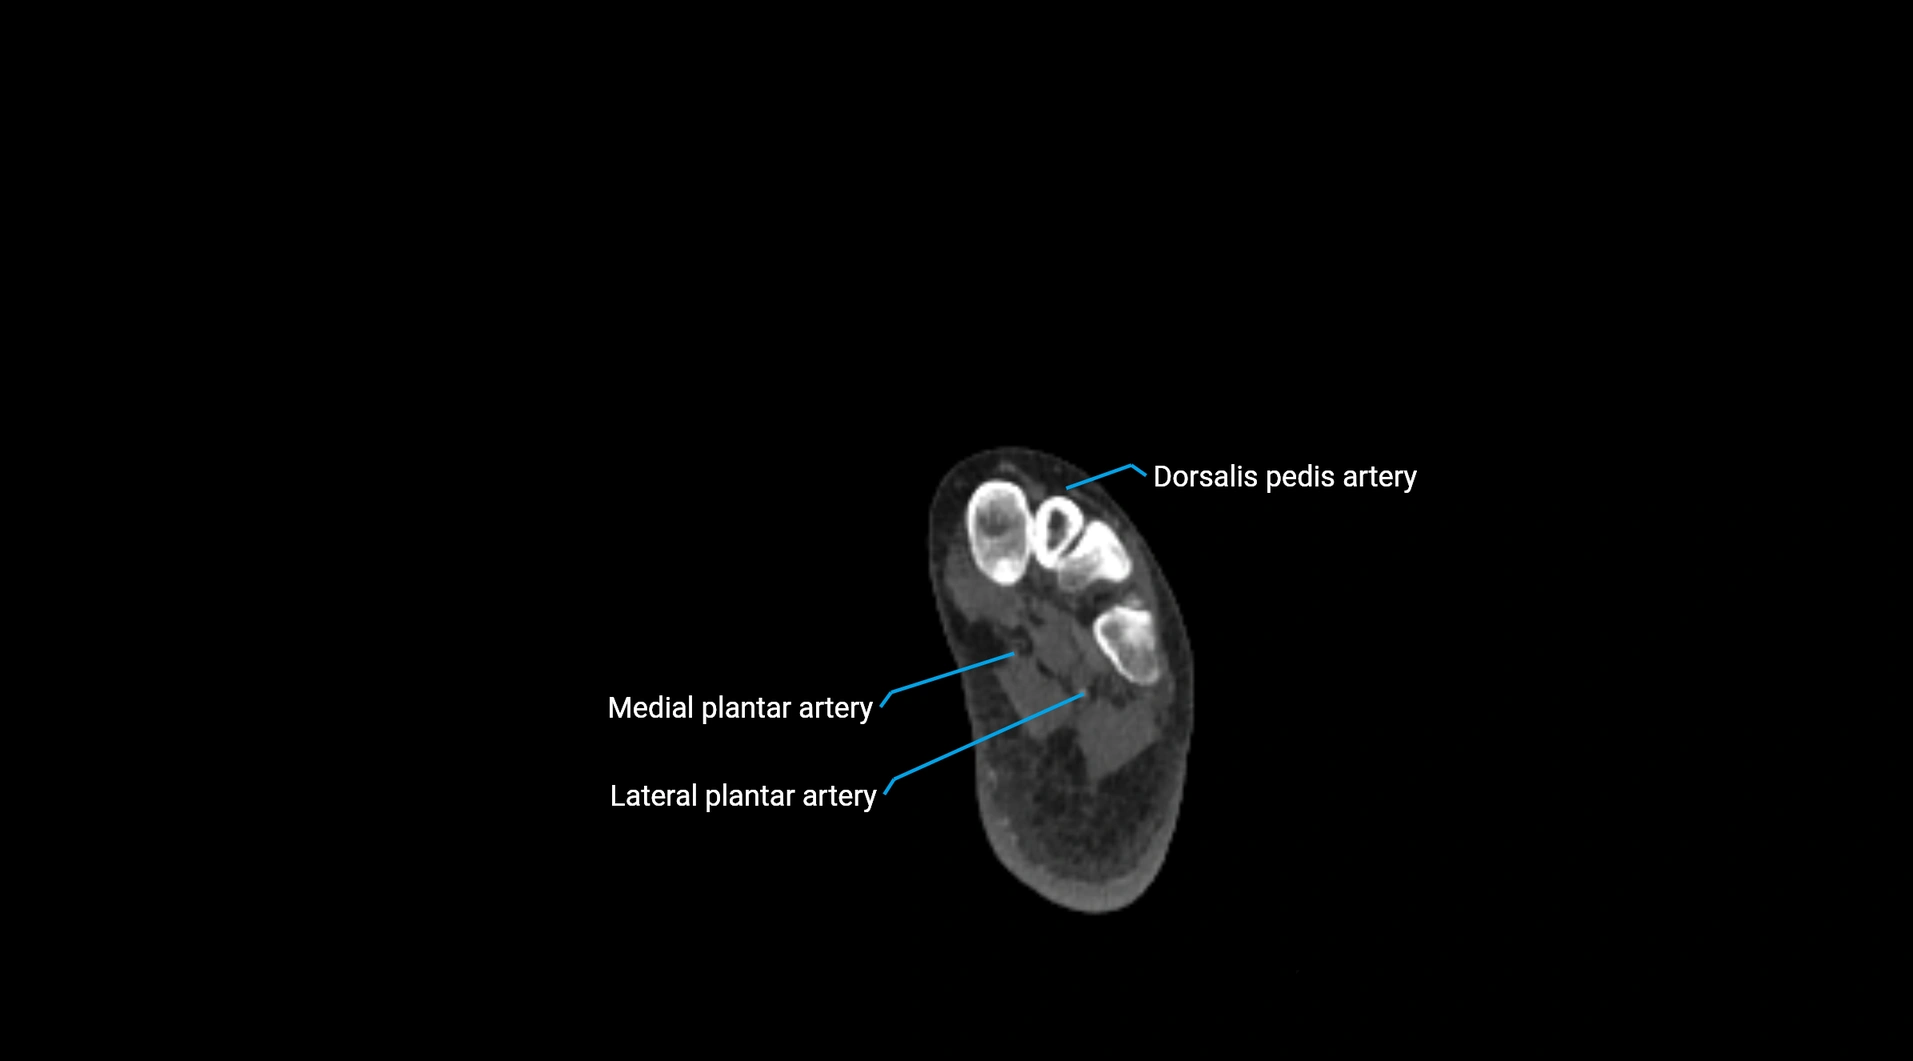

Contrast-enhanced CT (CTA):

• Gold standard for abdominal aortic imaging

• Provides excellent detail of lumen, wall, aneurysm, thrombus, and branch vessels

• Multiplanar and 3D reconstructions help in aneurysm measurement, stent graft planning, and dissection evaluation

• Detects acute rupture, traumatic injury, or occlusion with high sensitivity